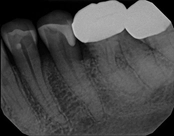

Upper molar failed root canal and apicoectomy:

Before

Immediately after

3-month follow-upThis person presented with one root that had failed from root canal treatment. The arrow in the picture, shows the infection as well as extra filling material that was pushed out of the root. An apical microsurgery was performed using the laser. The infection and excess material was cleaned out. Complete healing is visible 3 months after. The tooth was saved. This is a poor area for an implant.